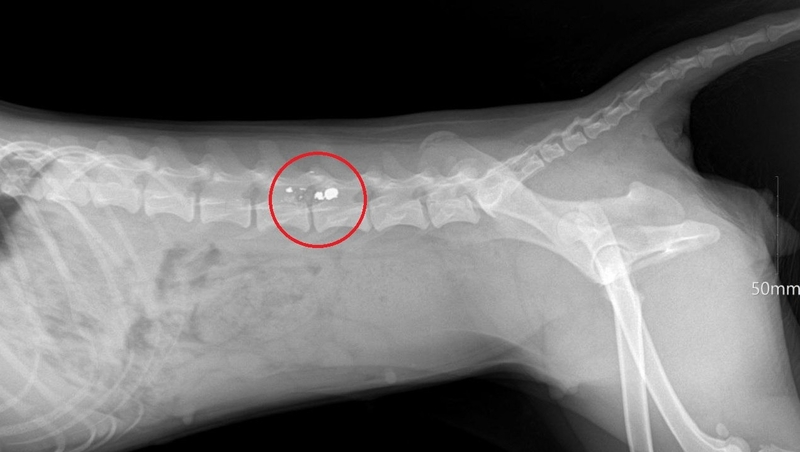

Ветеринары, осмотревшие животное, диагностировали паралич тазовых конечностей.